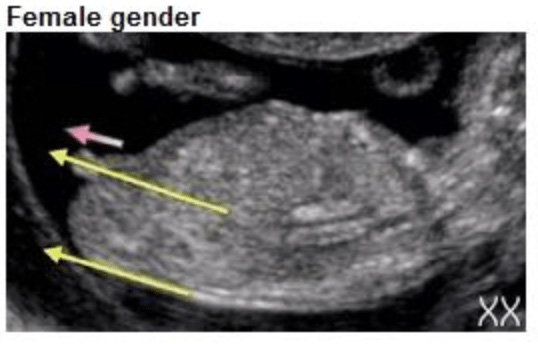

Het verschil? De hoek. Bij een jongen staat de nub in een hoek van meer dan 30 graden ten opzichte van de ruggengraat. Bij een meisje ligt de nub meer horizontaal, evenwijdig aan de ruggengraat.

• Bij een jongen: de nub begint omhoog te wijzen, in een hoek van 30 graden of meer ten opzichte van de ruggengraat. Hij groeit uit tot de penis.

• Bij een meisje: de nub blijft relatief vlak en horizontaal, evenwijdig aan de ruggengraat. Hij ontwikkelt zich tot de clitoris.

• Meisje: de nub loopt min of meer parallel aan de ruggengraat, of wijst zelfs iets naar beneden. Het uiteinde is vaak iets ronder of gegaffeld (gesplitst).

Echo met nub horizontaal langs de ruggengraat, kenmerkend voor een meisje

Nub meisje (horizontaal)